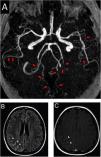

After four hours of the first IT chemotherapy infusion, the patient presented with severe headache, maximal at onset, described as a frontal and retro-orbital pressure, which persisted despite optimized analgesia, she did not show any other concurrent neurological signs or symptoms and her arterial blood pressure on admission was 110/70mmHg. Patient had received the last systemic chemotherapy 3 days before symptoms onset and denied receiving any other vasoactive drugs. Head computed tomography (CT) did not show any abnormalities, thus symptoms were initially attributed to post puncture headache. As she persisted presenting recurrent headache in the following days, a brain magnetic resonance imaging (MRI) and angiography was obtained 11 days after symptoms onset. Images showed signs of diffuse arterial vasospasms consistent with RCVS (Fig. 1A) with secondary subarachnoid hemorrhage (Figs. 1B and 1C). The patient was treated symptomatically and experienced gradual improvement of the headache within three weeks. Neuroimaging after twelve weeks showed complete resolution of the vascular findings and the previous hemorrhage.

Brain magnetic resonance and angiography images. A, Angiography MRI showing segmental arterial constriction (red arrows). B, High intensity signal in the cortical sulcus and gyrus of the right parieto-occipital convexity on T2/Flair (white arrowheads). C, Slight impregnation of contrast in the leptomeningeal adjacent to the right parieto-occipital convexity on T1-GD (white arrowheads).